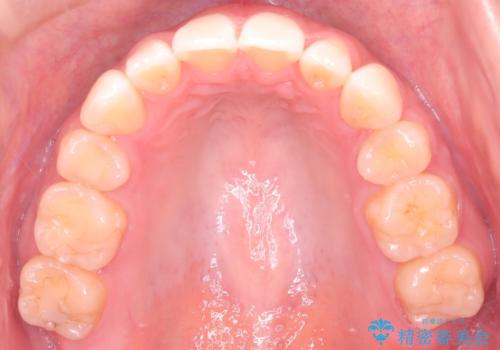

【審美装置】前歯のがたがたを治したい

- 前歯の凸凹と口元の突出感を主訴に来院されました。

臼歯関係が上顎前突傾向のため、上の小臼歯を抜歯してワイヤー矯正を行なっております。

下顎の叢生はIPRを行なって配列しています。